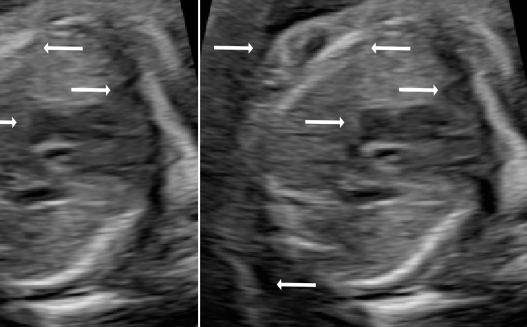

Three in vivo Bmode fetal images with and without aberration correction are presented in Figs. 10-12. GIF images of examples A-L (see Fig. 9 and Table 5) alternating between the corrected and uncorrected images are uploaded as supplementary material. The differences in image quality are easier to appreciate in the GIFs than in a side-by-side comparison. The data points for the three examples are colored black in Fig. 9. Table 5 give tabular values for the global sound speed estimate, sharpness increase (κ𝜅\kappaitalic_κ) and answers from the clinical evaluations.

Each aberration-corrected Bmode image is gained to have the same 80th percentile pixel intensity value as the 80th percentile value of the corresponding uncorrected image. The Bmode images are plotted in dB relative to the max of the uncorrected image.

Figure 10: Example A. In vivo fetal Bmode image using constant 1540 m/stimes1540dividemetersecond1540\text{\,}\mathrm{m}\text{/}\mathrm{s}start_ARG 1540 end_ARG start_ARG times end_ARG start_ARG start_ARG roman_m end_ARG start_ARG divide end_ARG start_ARG roman_s end_ARG end_ARG and the estimated average sound speed map. The average sound speed map is shown in the top right corner and the rightmost colorbar indicates the sound speed values. Alternating GIFs are found in the supplementary material.

Figure 11: Example B. In vivo fetal Bmode image using constant 1540 m/stimes1540dividemetersecond1540\text{\,}\mathrm{m}\text{/}\mathrm{s}start_ARG 1540 end_ARG start_ARG times end_ARG start_ARG start_ARG roman_m end_ARG start_ARG divide end_ARG start_ARG roman_s end_ARG end_ARG and the estimated average sound speed map. The average sound speed map is shown in the top right corner and the rightmost colorbar indicates the sound speed values. Alternating GIFs are found in the supplementary material.

Figure 12: Example C. In vivo fetal Bmode and coherence images using constant 1540 m/stimes1540dividemetersecond1540\text{\,}\mathrm{m}\text{/}\mathrm{s}start_ARG 1540 end_ARG start_ARG times end_ARG start_ARG start_ARG roman_m end_ARG start_ARG divide end_ARG start_ARG roman_s end_ARG end_ARG and the estimated average sound speed map. The average sound speed map is shown in the top right corner and the rightmost colorbar indicates the sound speed values. Alternating GIFs are found in the supplementary material.

The in vivo examples A-C, in Figs. 10-12 respectively, show different nuances of how sound speed aberration correction improves focusing quality. A noticeable improvement in Fig. 10 is the improved contrast and clarity of borders. The sound speed correction seems to remove the double structure indicated by the arrows in Figs. 10c-10d. The skull border and the brain structures in Fig. 11 are also better defined and clearer after aberration correction. Example C in Fig. 12 is the image with the highest increase in Tenengrad κ𝜅\kappaitalic_κ, seen from Fig. 9 and Table 5. The improvement in image quality is evident around the boundary of the fetus body and the correction sharpens the structures indicated by the arrows. The improved contrast between the layers in the shallow tissue layers is also noticeable.